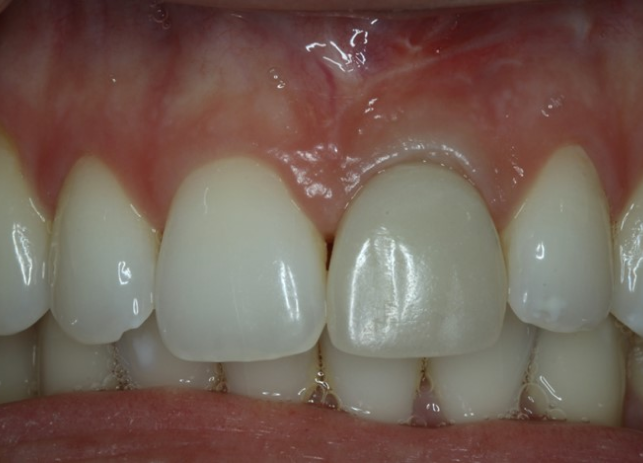

Рис. 23 Итоговый результат лечения с установленным мостовидным протезом 12-22 на имплантатах. Обратите внимание на естественный профиль ткани после извлечения 12, 11, 21 и 21